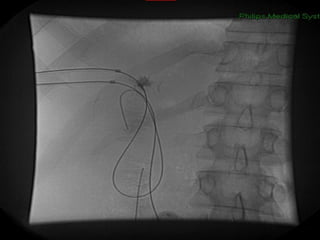

PAPEL DO RADIOLOGISTA DX TTO

Internalização dos Drenos

TROCA DE DRENOS